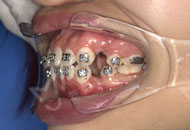

摘牙套前最後的一次拍照了,先看看牙,整齊啦! 醫生說等完全排齊後我就直接可以脫掉這些金屬的東西了,想想好開心,吃盤龍蝦獎勵自己~~

欲速則不達! 矯牙按部就班,醫生說我排齊的不錯,就是還有點咬合的問題,不過後期都是慢慢可以調整的,也是很nice了! 另外托槽,皮筋,橡皮鏈這些如果掉了要及時去找醫生黏貼好,如果你等到下次複診再去,那麼這段時間很有可能你的牙正在走彎路。 也就延長你整牙時間了。